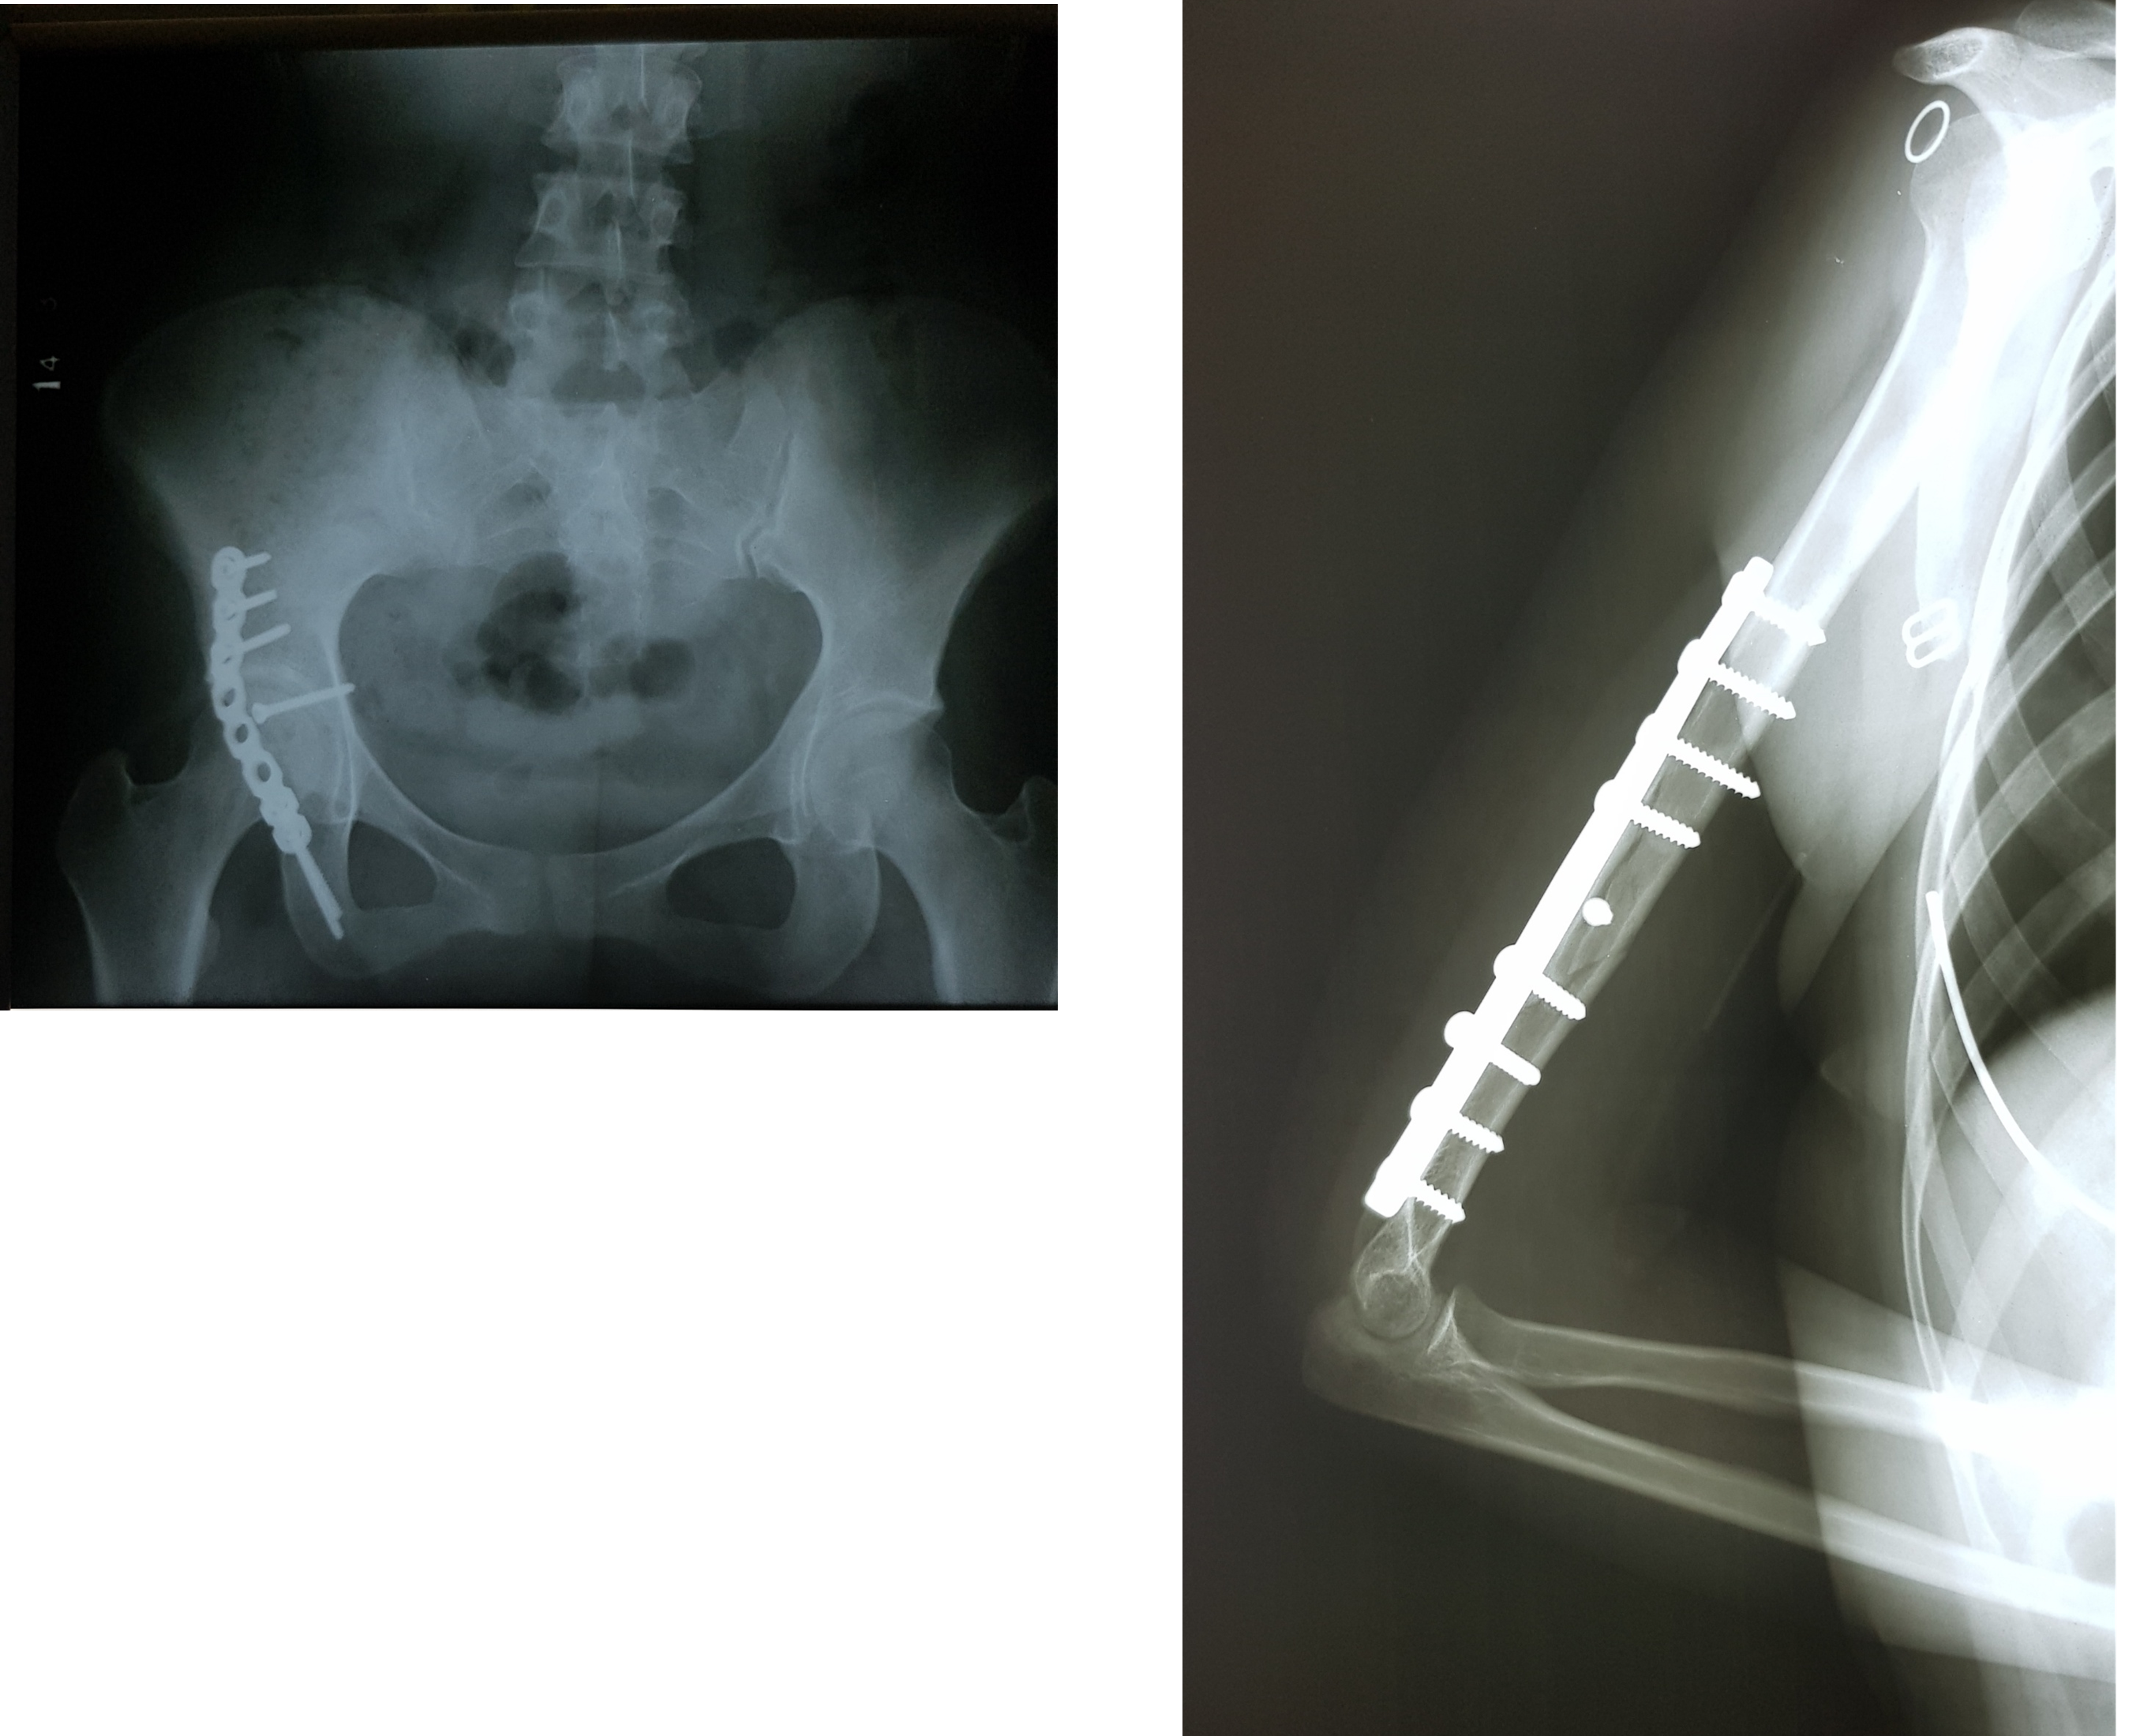

FRACTURA DE ACETABUL O DERY HÚMERO IZQUIERDO